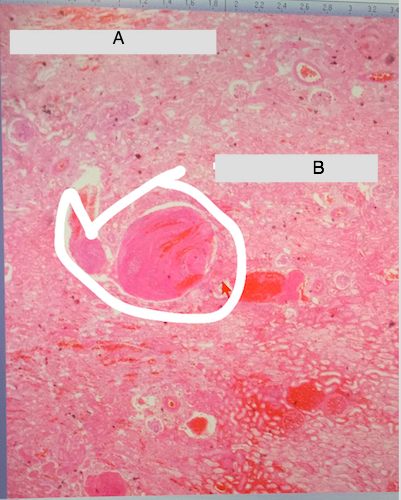

Label this photo